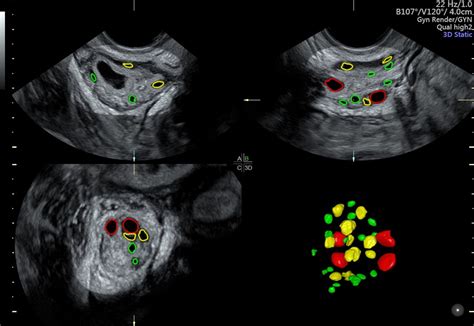

The Antral Follicle Count refers to the number of small follicles (2-10 mm in diameter) visible in the ovaries during an early follicular phase ultrasound. These follicles are crucial because they represent the pool of eggs that could potentially mature and be released during the menstrual cycle. The count is usually performed between days 2 and 4 of the menstrual cycle to ensure accuracy.

The measurement of Antral Follicle Count involves a transvaginal ultrasound, which is a non-invasive procedure. Here’s a step-by-step overview of the process:

• Preparation: The ultrasound is typically scheduled for the early follicular phase of the menstrual cycle, usually between days 2 and 4.

• Procedure: A transvaginal ultrasound probe is inserted into the vagina to get a clear view of the ovaries.

• Counting Follicles: The ultrasound technician counts the number of follicles in each ovary that measure between 2 and 10 mm in diameter.

• Reporting: The total count from both ovaries is recorded as the Antral Follicle Count.